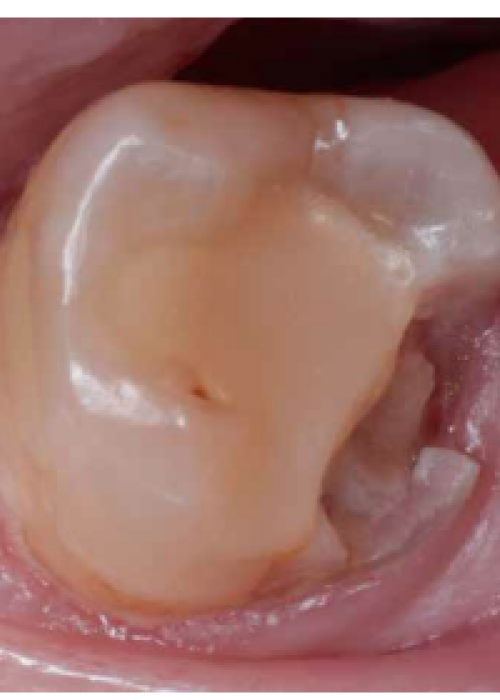

¿Es la pulpotomía una alternativa al tratamiento de conductos para los dientes con síntomas de pulpitis irreversible? A propósito de un caso